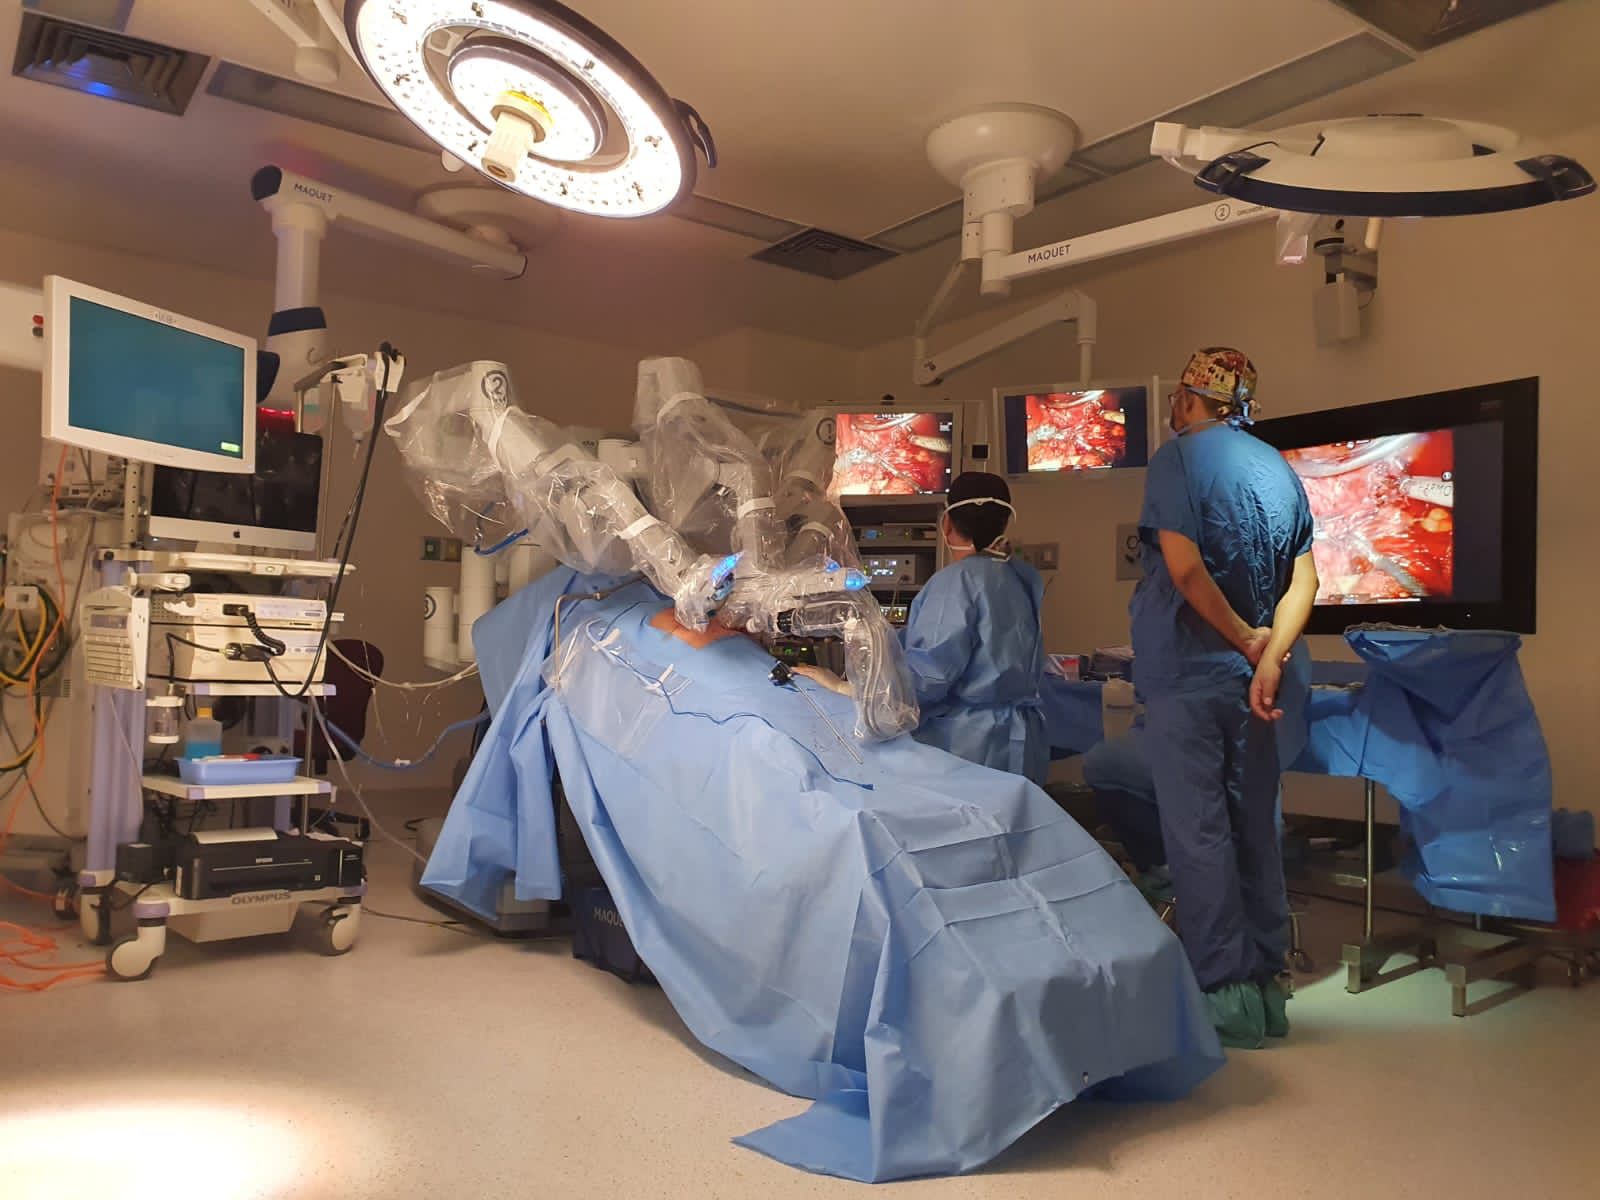

La cirugía robótica o asistida por robot, permite a los cirujanos hacer muchos tipos de procedimientos complejos con mayor precisión, flexibilidad y control en comparación con las técnicas convencionales.

El sistema robótico cuenta con un brazo para la cámara y 3 brazos mecánicos, e instrumentos quirúrgicos montados en ellos. El cirujano controla los brazos mientras está sentado frente a una consola de computadora cerca de la mesa quirúrgica. La consola proporciona al cirujano una visión tridimensional aumentada de alta definición del sitio quirúrgico.